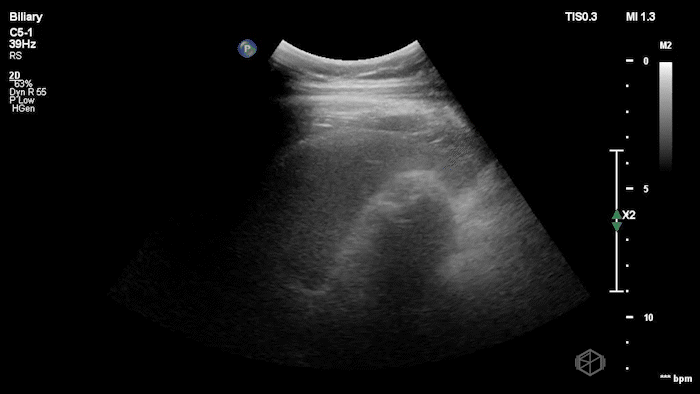

Dr. Mendelow performed a POCUS within 5 minutes that showed the following:

This scan shows a gallbladder filled with stones as indicated by the bright hyperechoic stones with shadowing posteriorly and almost no visible gallbladder wall lumen. This is consistent with a Wall-Echo-Shadow (WES) sign or configuration. The patient had a significantly elevated lipase and total bilirubin indicating gallstone pancreatitis. Radiology ultrasound resulted 90 minutes later with similar findings.

Diagnosis: Gallstone pancreatitis; WES sign